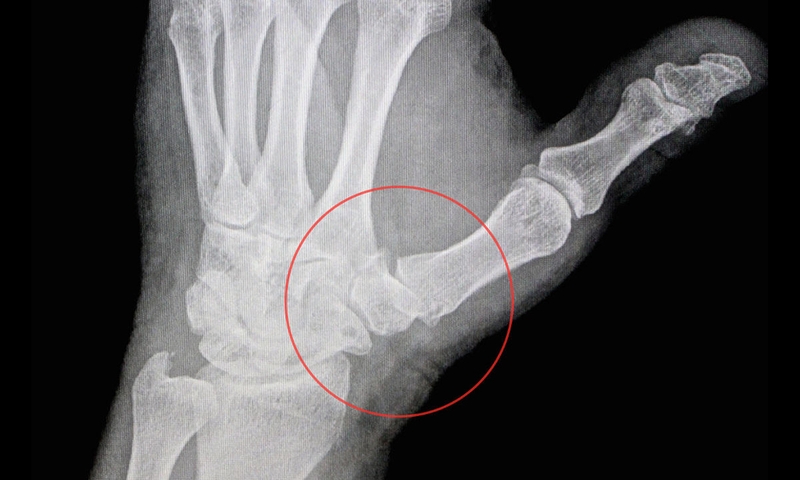

Một số chấn thương như gãy xương, bong gân… cũng gây nên tình trạng đau khớp tay cái. Các mô sụn bao phủ đầu xương, đóng vai trò như một lớp đệm lót, cho phép các xương trượt lên nhau. Tuy nhiên, khi bị tổn thương, các mô sụn bị giảm chất lượng làm cho bề mặt trơn nhẵn tại các đầu khớp bị sần sùi. Khi đó, các đầu xương chà xát vào nhau sẽ dẫn đến sự ma sát và tổn thương khớp, làm đau khớp tay cái.

Các tổn thương này có thể dẫn đến sự xuất hiện của xương mới, tăng trưởng dọc theo hai bên của xương hiện tại. Gây nên các khối u trên khớp tay ngón cái của người bệnh.